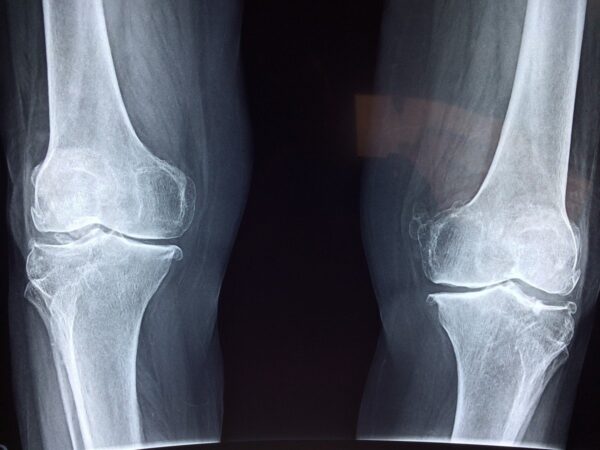

Arthrose ist in Deutschland die häufigste aller Gelenkerkrankungen. Bei rund 18 Prozent der Erwachsenen ist die Knorpelschicht eines Gelenks zerstört, dass sie unter starken Schmerzen und Entzündungen leiden. Im Extremfall führt die Krankheit bis zur Bewegungsunfähigkeit und zum Gelenkersatz. Weltweit ist Arthrose ebenfalls die häufigste Gelenkerkrankung, unter der etwa 200 Millionen Menschen leiden.

Laut Informationen der Deutschen Arthrose-Hilfe leiden in Deutschland etwa fünf Millionen Menschen unter Arthrose, Tendenz steigend. Am häufigsten betroffen sind Hände, Knie und Hüften, es können aber auch alle anderen Gelenke befallen sein. Ältere Menschen leiden zwar häufiger unter einer Arthrose als jüngere, trotzdem betonen Ärzte, Arthrose sei kein altersbedingter Verschleiß.

Dennoch leiden ältere Menschen häufiger unter Arthrose als jüngere. Ab dem 60. Lebensjahr ist es gut die Hälfte der Frauen und ein Drittel der Männer, vor dem 30. Lebensjahr nur 1,6 Prozent. Auch die verschiedenen Arten der Arthrose sind sehr unterschiedlich verteilt. Bei einer Hüftgelenk-Arthrose sind beide Geschlechter gleichermaßen betroffen, Frauen leiden im Alter aber doppelt so häufig an einer Arthrose der Knie- und Fingergelenke wie Männer. In Deutschland haben bereits vier Millionen Menschen ein künstliches Gelenk. Bisher wird die Diagnose Arthrose allerdings oft viel zu spät gestellt.

Da Knorpelschäden auf Röntgenbildern oder MRT-Aufnahmen erst in einem späteren Stadium zu sehen seien, wenn der Knorpel abgenommen hat und so dünn geworden ist, dass sich der Gelenkspalt verschmälert hat und Knochen droht, auf Knochen zu reiben, sei eine Früherkennung der Arthrose aktuell noch nicht möglich, so Wolf. Bei der Diagnose sei der Knochen dann meist schon so beschädigt, dass nur noch ein neues Gelenk infrage käme. „Wenn wir schon früh herausfinden könnten, dass eine Arthrose beginnt, könnte man rechtzeitig therapeutisch entgegenwirken, etwa mit Kompressionsbehandlungen oder Krafttraining“, hofft der Physiotherapeut Wolf.